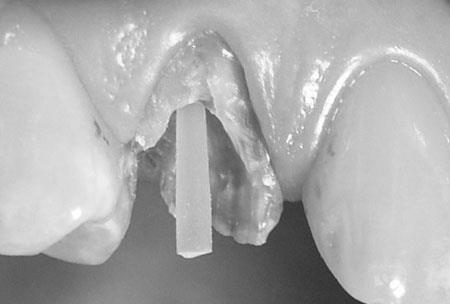

Na zdjęciu poniżej mamy pokazany wkład z włókna szklanego wystający z kanału. Należy wokół niego odbudować cementem lub kompozytem brakujące tkanki.

Ogromną zaletą wkładów z włókna szklanego jest ich biokompatybilność oraz neutralny, białawy kolor.